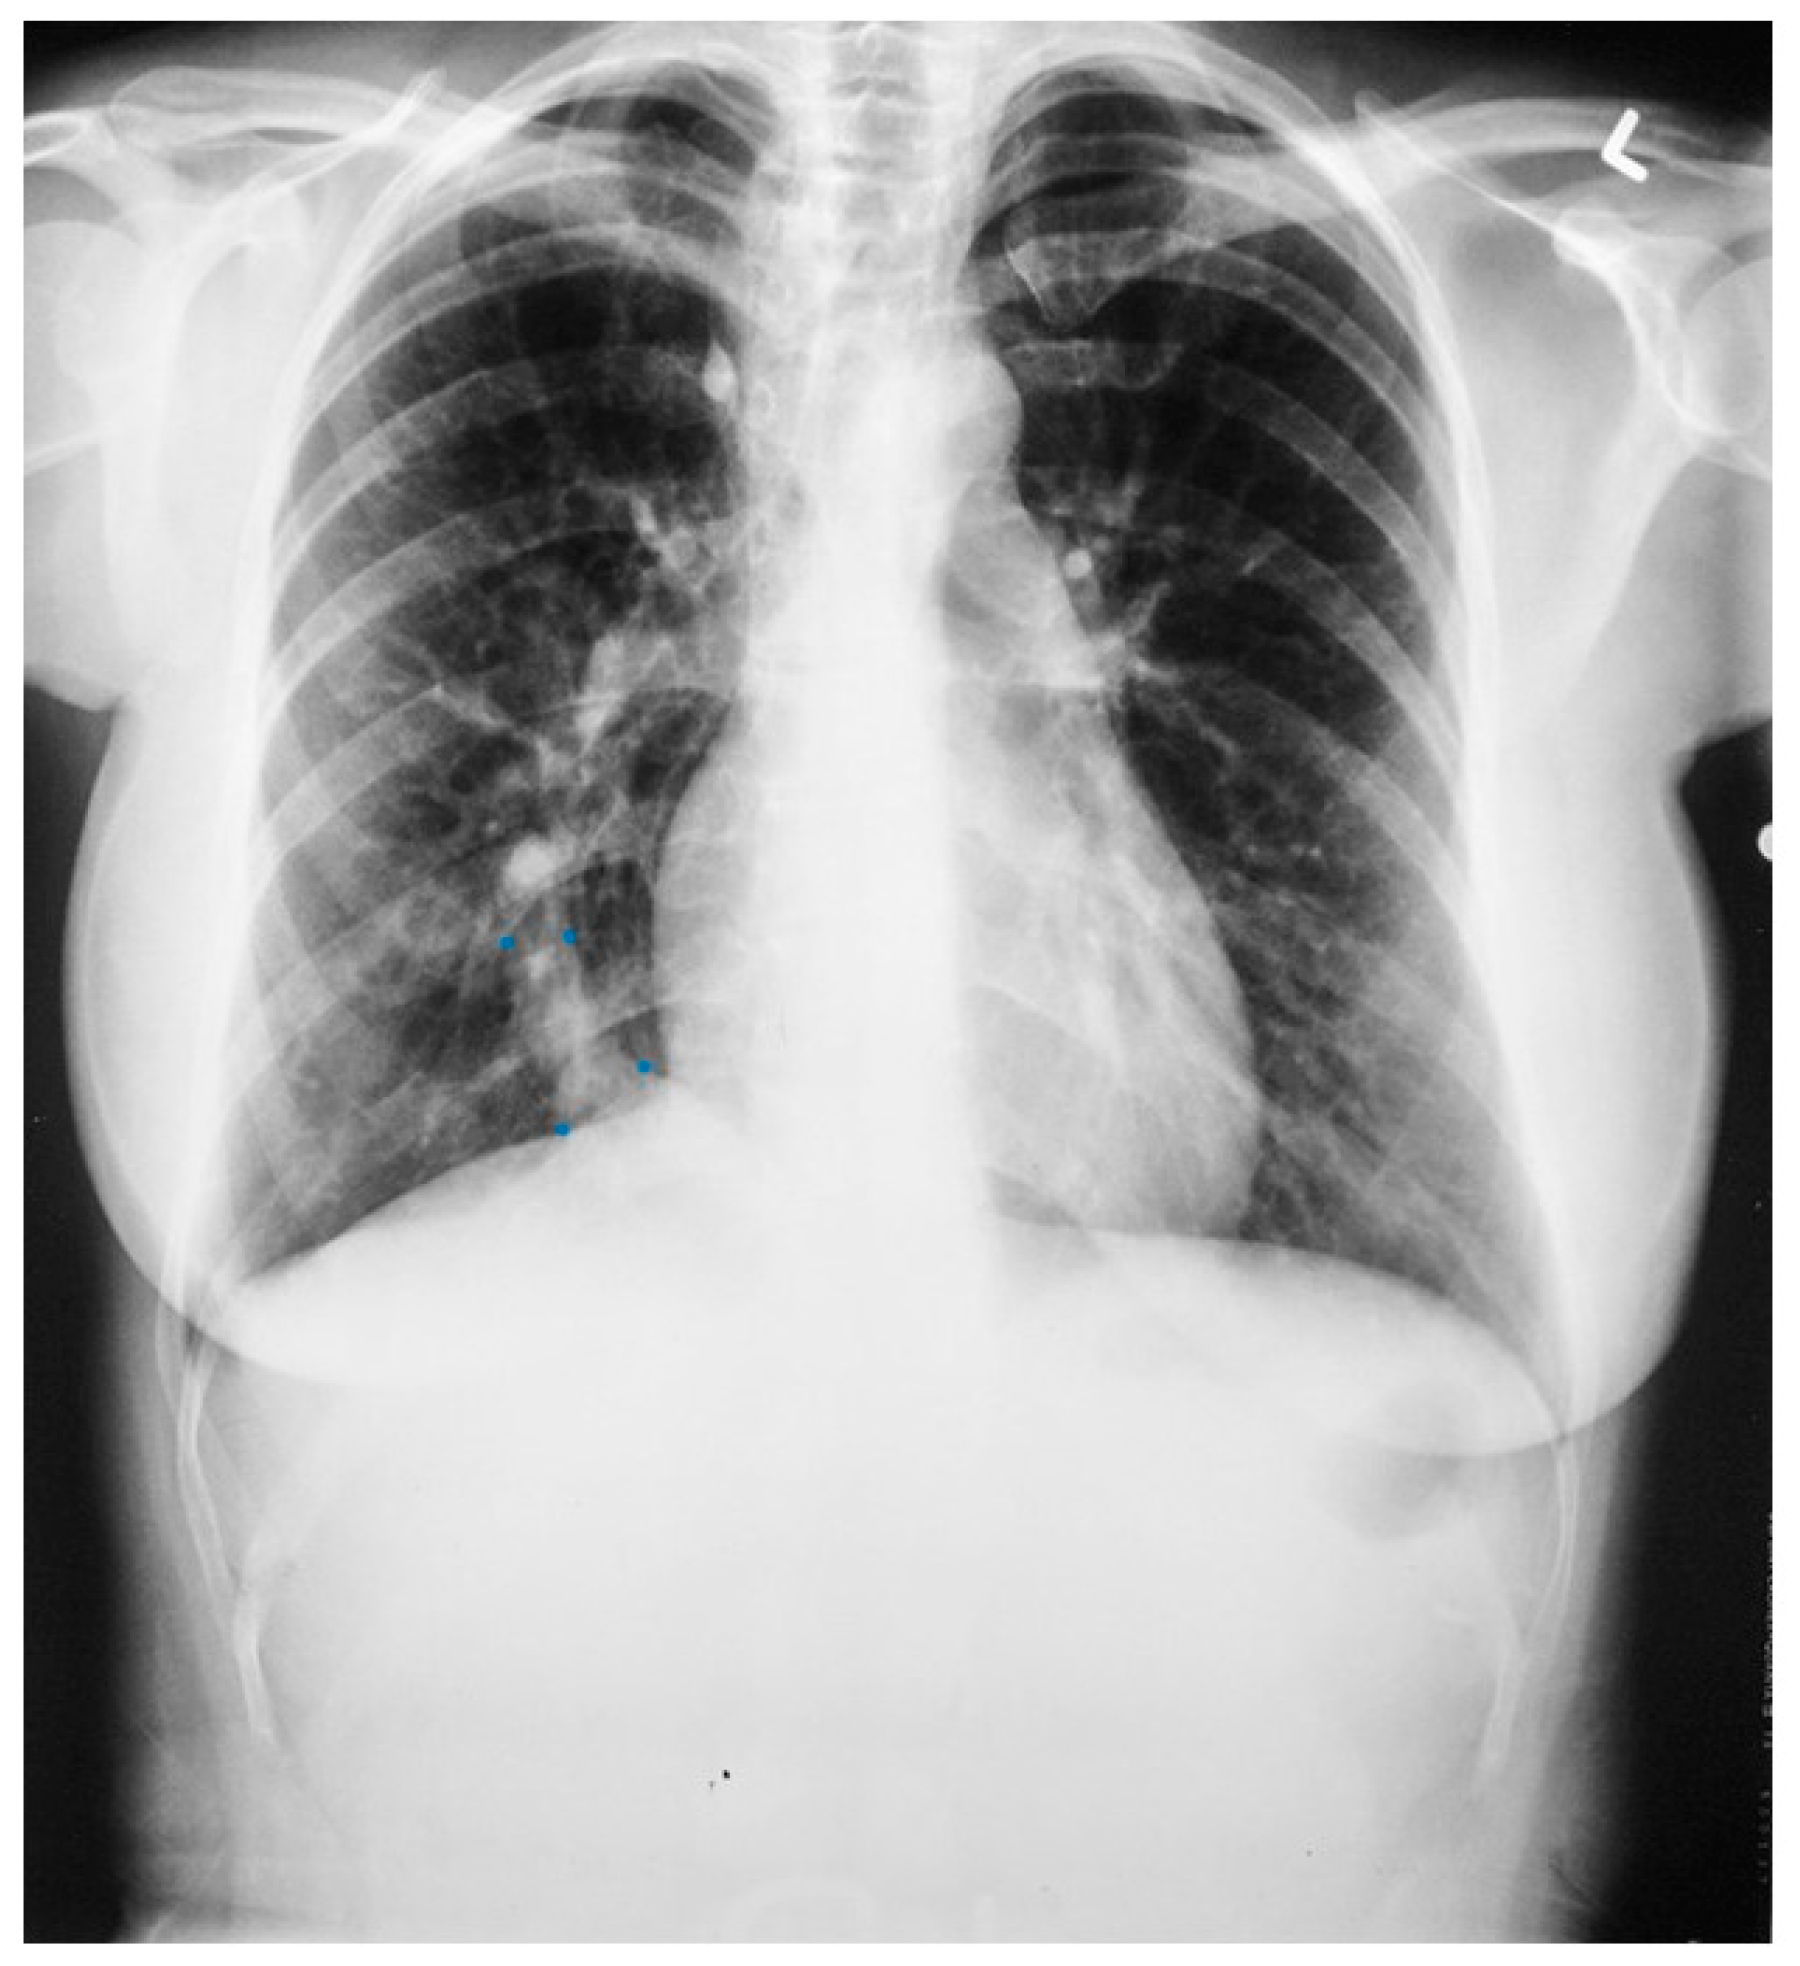

Figure 23.

Posteroanterior chest X-ray in an adult with previously operated tetralogy of Fallot: the chest X-ray was obtained in a 21-year-old female with exertional dyspnea. She was cyanotic at birth and diagnosed with tetralogy of Fallot. She had a Blalock-Thomas-Taussig (BTT) shunt (palliative subclavian artery to pulmonary artery shunt) at 10-months-of-age. At 3-years-old she underwent complete repair with closure of the ventricular septal defect, right ventricular (RV) outflow tract reconstruction with pericardium, with transannular patch and ligation of the BTT shunt. This posteroanterior chest X-ray is well centered and the inspiration is good. The cardiothoracic ratio is increased and the cardiac silhouette is boot-shaped (“coeur en sabot”). The right heart border is prominent, suggesting right atrial enlargement. The pulmonary vascularity is normal and the lung fields and pleura are clear.